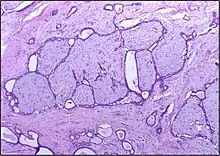

Macroscopic view of fibroadenoma of the breast

Closeup of a fibroadenoma of the breast

Macroscopic

Approximately 90% of fibroadenomas are less than 3 cm in diameter. However, these tumors have the potential to grow reaching a remarkable size, particularly in young individuals. The tumor is round or ovoid, elastic, and nodular, and has a smooth surface. The cut surface usually appears homogenous and firm, and is grey-white or tan in colour. The pericanalicular type (hard) has a whorly appearance with a complete capsule, while the intracanalicular type (soft) has an incomplete capsule.[11]